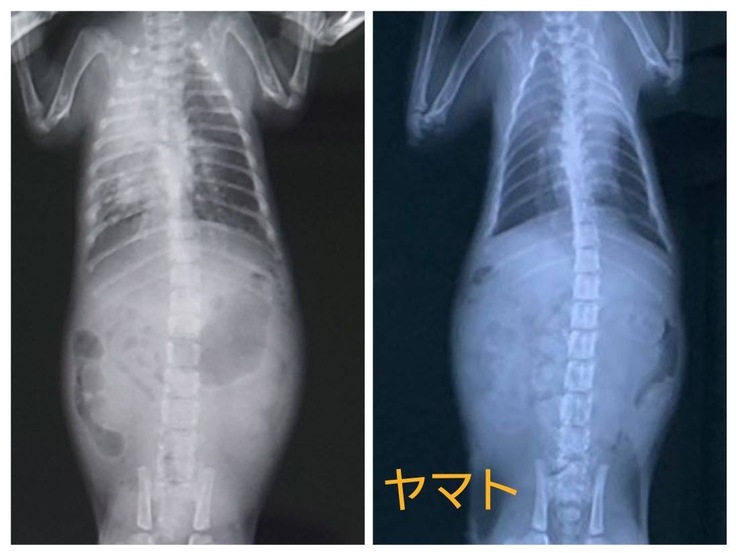

退院時(左)と現在(右)の肺のレントゲンを比べてみました。2匹ともまだ少しモヤはかかっていますが、だいぶ綺麗になりました。

ヤマトはトイレをするときにおしっこは伏せの体制、うんちは高い声で唸る(叫ぶ)ことが気になっており相談してきました。特にレントゲンで異常は見当たらないようですが、うんちをするっと出やすくするために、療法食(消化器サポート)の話が出ました。様子を見て療法食を使用していくかもしれません。また変化がありましたら報告いたします。